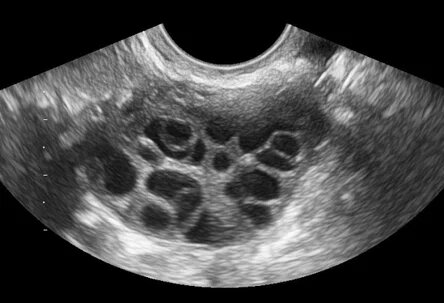

Если взять всех женщин с бесплодием, около 20-30% из них будут составлять женщины с СПКЯ (синдромом поликистозных яичников).

Поликистозный яичник.

СПКЯ - диагноз исключения. Прежде чем его поставить, мы должны исключить указанную выше патологию (гипотиреоз, гиперпролактинемию, нВДКН). СПКЯ - хроническое заболевание, чаще манифестирует с 21 лет, сопровождаясь нерегулярным циклом и/или наличием симптомов гиперандрогении (избыточный рост волос на лице и теле, выпадение волос на голове).